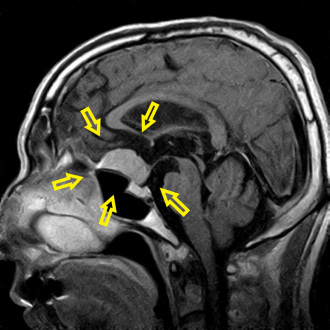

頭部MRIで脳腫瘍を認め、総合病院の脳神経外科に紹介しました。